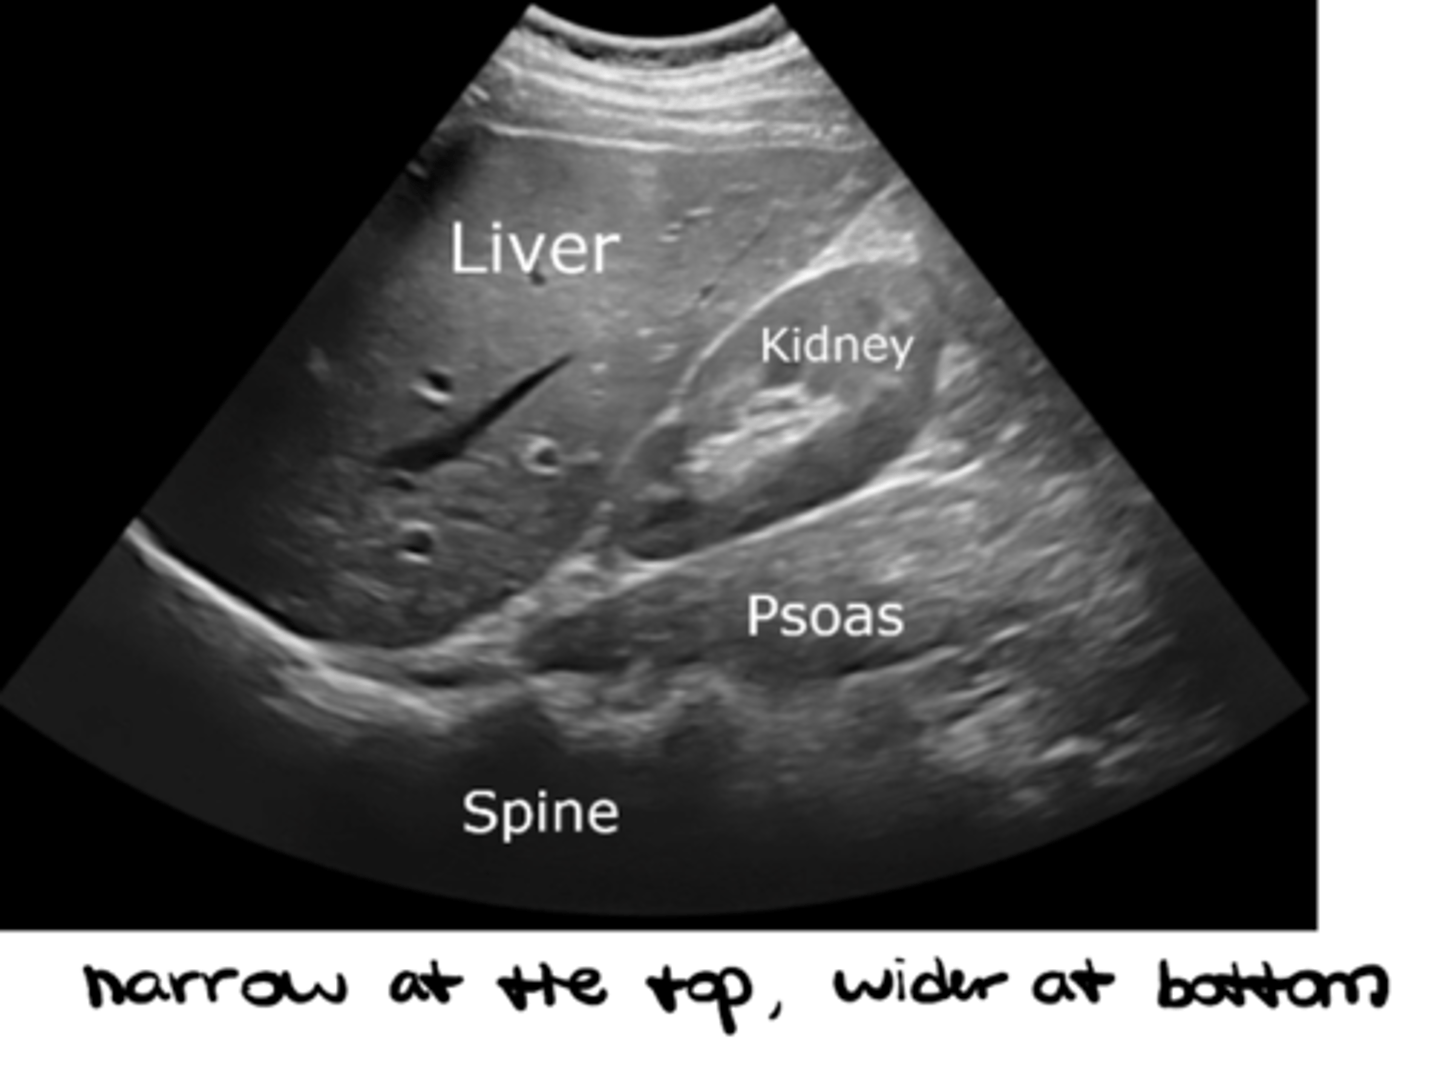

Which type of probe is MOST appropriate to view deep structures?

Curvilinear with LOW frequency (narrow at the top and wider at the bottom)